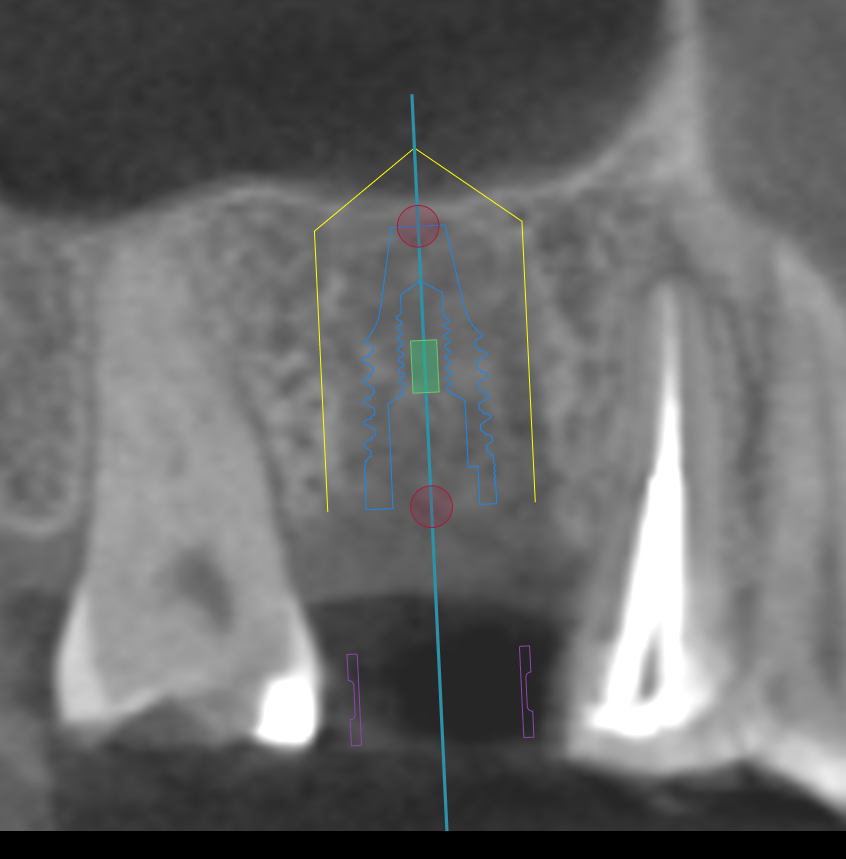

CT撮影

埋入位置を決めるための装置(ラジオグラフィックガイド)を口腔内に入れCTを撮影します。

【ラジオグラフィックガイド】

埋入ガイド

CT画像上にて決定した埋入位置で製作された埋入ガイド。正確でスムーズな手術を行えます。

【埋入ガイド】